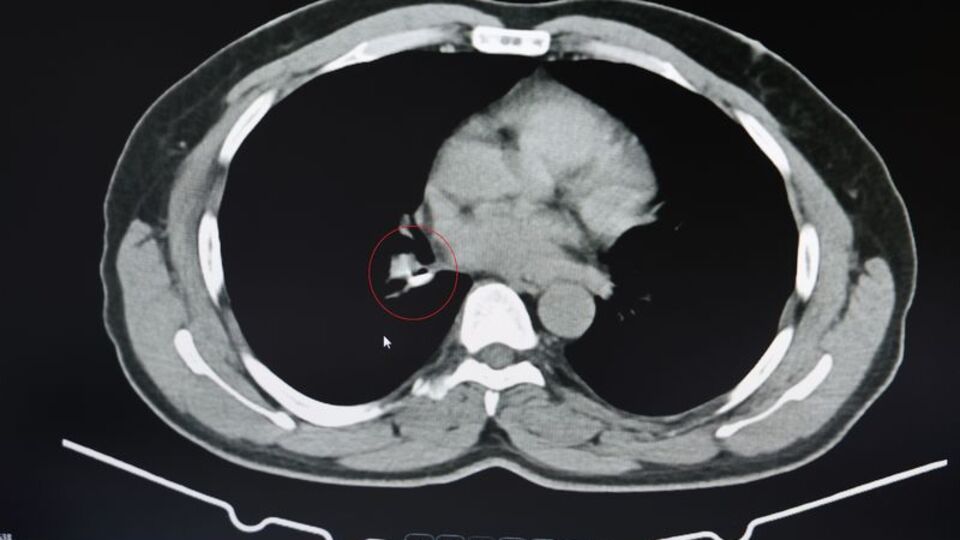

1.5 yıldır astım tanısından sonra tedaviler almaya başlayan İ.U., Prof. Dr. Abdurrahman Şenyiğit’in yanına geldiğinde yapılan tetkiklerde gerçek bambaşka çıktı. Yapılan tomografi ve bronskokopi işlemlerinde akciğere yerleşen maddenin yutulan silikon olduğu belirlendi. Silikonun çıkartılmasıyla hastanın şikayetlerinin ortadan kalktığı belirtildi.

Şenyiğit, o maddenin zamanla akciğer yapısının özelliğini aldığını ve orada yabancı bir madde olarak kaldığına değinerek, "Hastamıza maalesef 2 yıldan beri astım tanısı konulmuş ve sürekli tedavi verilmiştir. Hasta bize geldiği zaman yapılan tomografide sağ akciğer ana bronşun distalinde şüpheli lezyon gördük. Uyguladığımız bronskokopide yabancı maddenin silikon olduğunu tespit ettik. Onu çıkardıktan sonra da hastada bir rahatlama meydana geldi" dedi.